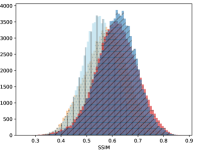

To visualise similarity metrics that compare image pairs (RMSE, SRE, SSIM) two metric distributions are generated: intra-similarity and inter-similarity. For each compared sample 300 random images are selected. The inter-similarity distribution is calculated for each image pair combination from both compared samples e.g. generated images of COVID-19 and real images of COVID-19. For the intra-similarity, all pairs of images in a single sample e.g real images of COVID-19 are considered. By comparing the shape of intra-similarity for the training subsample (Dataset) with the inter-similarity of training and generated samples the quality of the generated sample can be judged. It is also possible to compare in this way between the four image classes present in the dataset. The resulting distributions of inter-similarity of COVID-19 and the three remaining classes are compared in Fig. 4 to distributions of intra-similarity of the COVID-19 sample for each metric. All metrics, as expected based on available medical evidence Rubin et al. (2020), indicate that there are visible differences not only between COVID-19 and normal samples but also between viral pneumonia and lung opacity. Therefore, all classes should be distinguishable.

To visualise differences between synthetic and real samples distributions are generated for each of the RMSE, SRE and SSIM metrics: intra-similarity and inter-similarity. For each compared sample 300 random images are selected. The inter-similarity distribution is calculated for each image pair combination from both compared samples e.g. generated images of COVID-19 and real images of COVID-19. For the intra-similarity, all pairs of images in a single sample e.g real images of COVID-19 are considered. The distributions for generated samples describe very well the distributions for corresponding real images as shown in Fig. 6.

The quality of generated images is also confirmed with classical similarity metrics. The distributions of those similarity measures between generated and real images are compared for each sample with the distribution obtained within the real samples 6. The distributions for generated samples describe very well the distributions for corresponding real images. For an example see the results for the SSIM metric presented in Fig. 10. The small visible differences are almost insignificant compared to differences observed between the classes in Fig. 4.